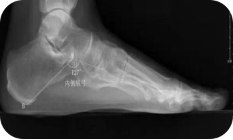

X线测量法:第一跖骨距骨角、距舟覆盖角及跟骨倾斜角等参数的测量,对足进行影像学评估。

足负重前后位、足负重侧位(足内弓角测量、外弓角测量、跟骨倾斜角)。